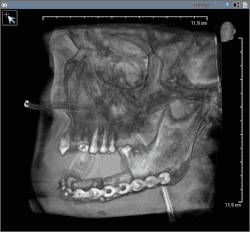

In most centres, removal of squamous cell carcinoma from the oral cavity and neck is achieved primarily through surgery. This also allows a detailed examination of the tissue for histopathologic characteristics, such as depth, and spread to lymph nodes that might require radiation or chemotherapy. For small lesions (T1–2), access to the oral cavity is through the mouth. When the lesion is larger, involves the bone of the maxilla or mandible, or access is limited due to mouth opening, the upper or lower lip is split, and the cheek pulled back to give greater access to the mouth.[45] When the tumor involves the jaw bone, or when surgery or radiation will cause severe limited mouth opening, part of the bone is also removed with the tumor.